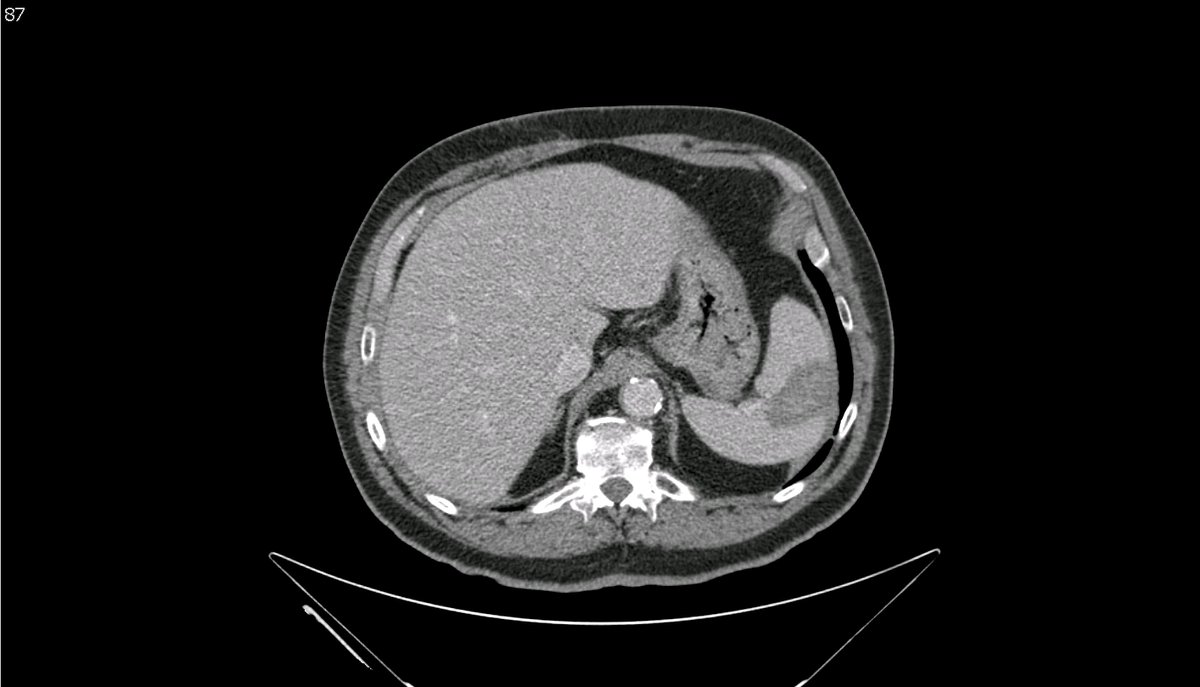

New study @AnnalsofIM bit.ly/2Km3KYu by @DrTalenfeld @WeillCornell: Percutaneous ablation for T1a #renalcancer has similar 5-year survival rates to radical nephrectomy but with far fewer 30-day complications and less #kidneyfailure.